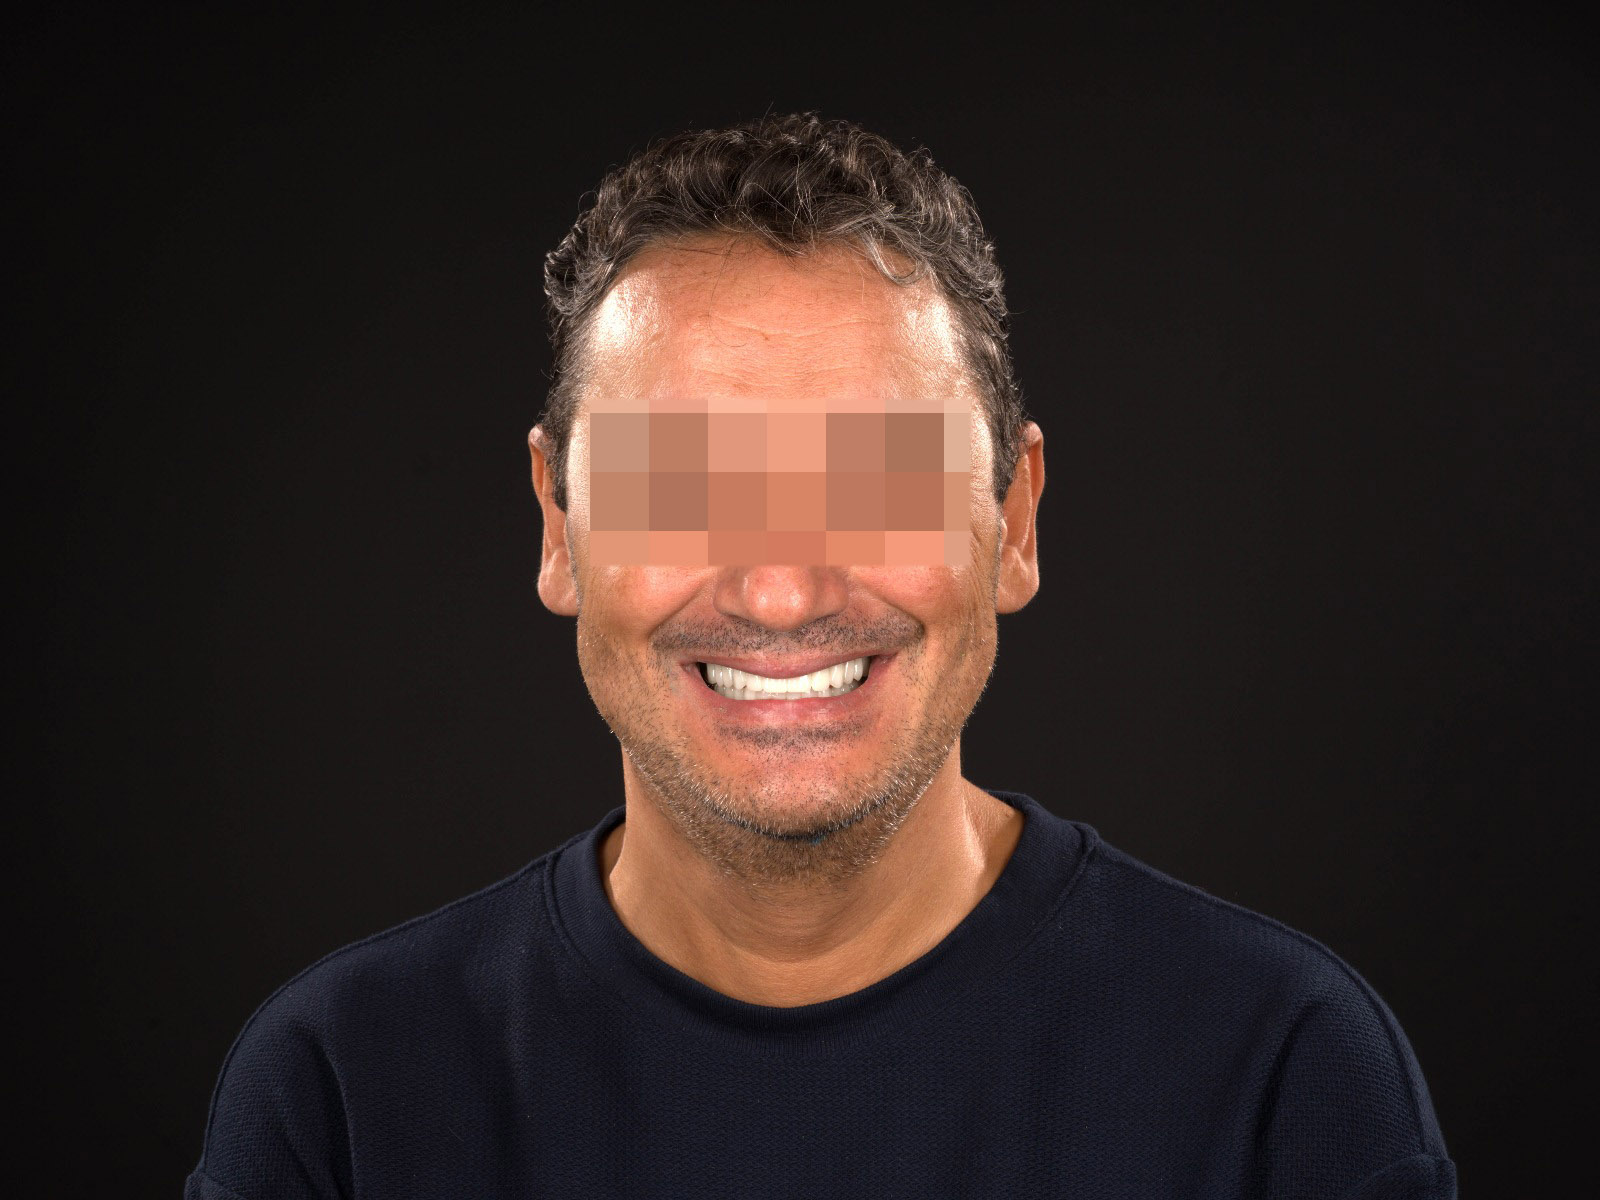

Pacientul s-a prezentat cu probleme estetice și funcționale majore, agravate de mobilitatea generalizată a dinților.

Am realizat o proteză fixă din zirconiu pe 8 implanturi la maxilarul superior și o proteză fixă din metalo-ceramică pe 7 implanturi la mandibulă.

Rezultatul: zâmbet stabil, funcțional și complet redobândit!

înainte

după